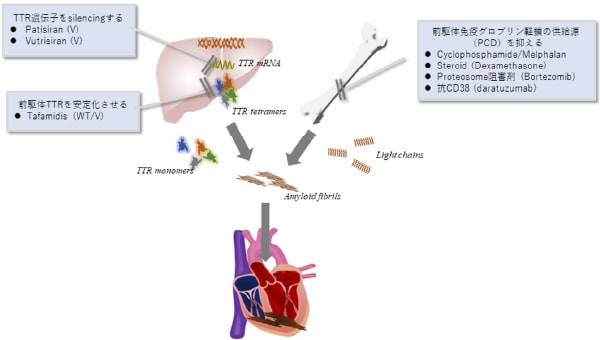

心アミロイドーシスでは、アミロイドという繊維質のような物質が心筋に沈着し、心肥大(壁肥厚)に伴う心不全や不整脈を併発する疾患です。アミロイドの前駆体がトランスサイレチンであるタイプ(ATTRアミロイドーシス:変異型ATTRvと野生型ATTRwtに分かれます)と前駆体が免疫グロブリン軽鎖であるALアミロイドーシスがあります。高齢者で良く見られるATTRwtの診断は心筋の壁肥厚や、心筋生検におけるアミロイド・前駆体沈着や核医学検査(99mTc-ピロリン酸シンチまたは99mTc-HMDPシンチ)などが有用です。

治療方法の発展のおかげで心アミロイドーシスに対しては前駆体ができるのを抑える治療が可能です。ATTRにはtafamidis、変異型ATTRにはPaticiranやVutrisiranが有効です。AL型にも最近有効な薬剤が登場してきました。